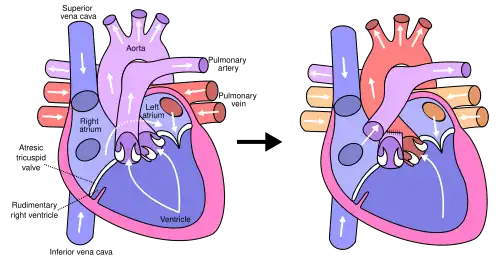

Die Fontan-Operation[1] wird heute (2004) als häufigste Palliativoperation bei komplexen angeborenen Herzfehlern durchgeführt, die sich mit einem Single Ventricle (Einkammerherz) darstellen. Zunächst vor allen Dingen bei der Trikuspidalatresie angewandt, gibt es heute eine Reihe von Modifikationen bei anderen Formen des Einkammerherzens. Auch die ursprüngliche Operationstechnik in einem Schritt wurde weiterentwickelt und wird heute in der Regel in zwei Operationsschritten vorgenommen.

und hat das Ziel, den bisher parallelen und gemeinsamen Kreislauf (mit hoher Volumenbelastung des Ventrikels) in zwei getrennte, in Serie geschaltete Kreisläufe zu verwandeln.

1. Glenn-Anastomose

Alle angeborenen oder operativ angelegten zentralen Zuflüsse zu den Lungenschlagadern werden unterbrochen. Das ist in der Regel die Durchtrennung des Truncus pulmonalis (als deren Hauptstammes), der Verschluss eines noch bestehenden Ductus arteriosus und der Verschluss vorher angelegter aorto-pulmonaler Shunts. Die obere Hohlvene (VCS) wird durchtrennt und mit der rechten[2] Pulmonalarterie (Lungenschlagader) verbunden. Die aktuell verwendete Modifikation ist die sogenannte Glenns Zwei-Wege-Anastomose - eingeführt von Azzolin, die die obere Hohlvene im Lungenstamm mit dem Zufluss von venösem Blut aus dem VCS zu beiden Lungen (bidirektional - zur linken und rechten Lunge) verbindet.[3] Der herznahe Anteil wird blind verschlossen. Die untere Hohlvene leitet ihr Blut unverändert in die Hauptkammer. Dadurch besteht weiterhin eine Zyanose, jedoch geringer als vor der Operation.

2. Fontan-Komplettierung = Totale cavo-pulmonale Anastomose (total cavo-pulmonary Connection = TCPC)

Das Blut der unteren Hohlvene wird über eine Kunststoffprothese (GoreTex-Patch) durch (intrakardial) den rechten Vorhof (Atrium) ebenfalls zur Pulmonalarterie geleitet; es wird also eine Verbindung von unten geschaffen, so dass nun auch das Blut aus der unteren Hohlvene direkt in das Lungengefäßsystem geleitet wird. In diesen Patch, der das durchfließende venöse (sauerstoffarme) Blut vom funktionslosen rechten Vorhof trennt (dieser wird durch die Entfernung der verbliebenen Reste der Vorhofscheidewand (Septum atriale) mit dem linken Vorhof verbunden), wird ein kleines Loch gestanzt (Fenestrierung), welches als Überlaufventil für die erste Zeit dient, falls die Lunge noch nicht das gesamte Blut aus dem Körperkreislauf aufnehmen kann. Dieses Loch schließt sich möglicherweise von selber oder wird im Rahmen einer Herzkathetersitzung verschlossen, wenn es für die Herz-Kreislauf-Funktion nicht mehr notwendig ist.

Arterieller und venöser Blutfluss sind jetzt getrennt. Es besteht nach der TCPC (im Gegensatz zur Glenn-Anastomose, wo sich noch arterielles und venöses Blut aus dem unteren Körperbereich mischen) keine Zyanose mehr. Durch die Umleitung des venösen Blutes aus dem Körperkreislauf ohne funktionell wirksame rechte Herzkammer direkt in den Lungenkreislauf werden Körperkreislauf und Lungenkreislauf hintereinander gepumpt. Der Druck aus dem Körperkreislauf reicht aus, um den Lungenkreislauf mitzupumpen. Das ist möglich, wenn der Lungengefäßwiderstand nicht zu hoch ist. Deshalb ist diese Operation bei Patienten, bei denen sich eine pulmonale Hypertonie entwickelt hat oder der Lungengefäßwiderstand zu hoch ist, nicht möglich.